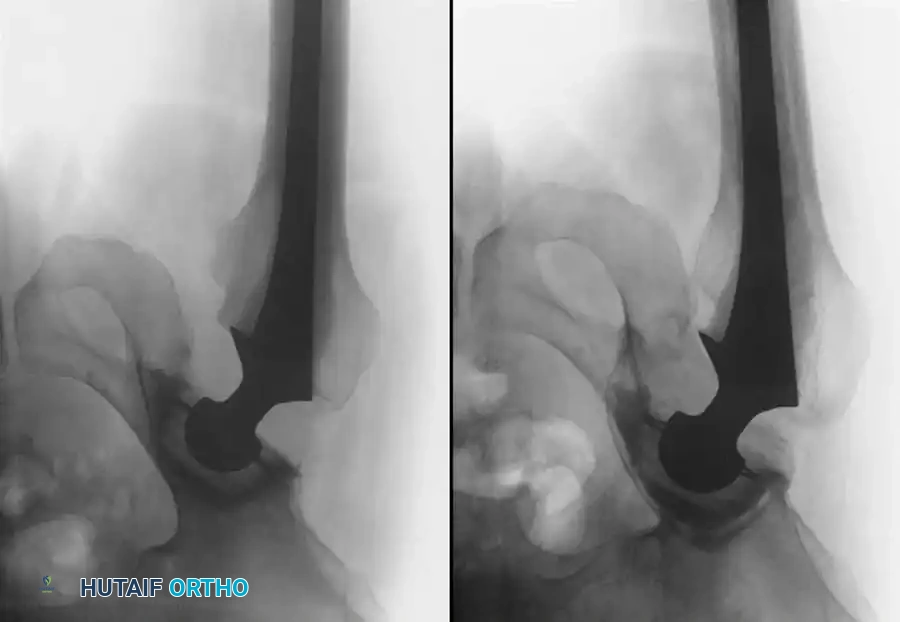

Late bleeding (≥ 1 week postoperatively) may occur secondary to a false aneurysm. In such cases, arteriography is required for the precise identification of the affected vessel, often followed by therapeutic embolization.